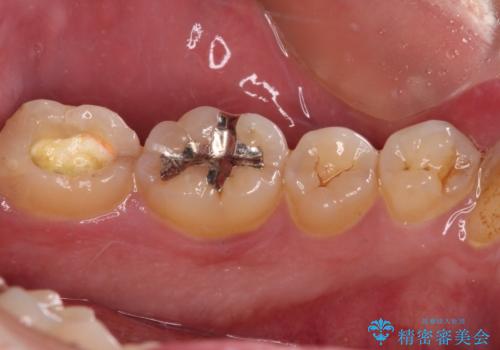

- 職場近くで通っていた医院の先生が体調不良で診療できなくなったとのことで、転院されてきた患者様です。

既に根管治療を終えている状態での来院で、クラウンを装着を希望されていらっしゃいました。

レントゲン写真より根管治療のやり直しをお勧めしたところ、ラバーダム使用下で処置を行うことを希望されたため、根管治療を行った後にオールセラミッククラウンにて補綴治療を行うこととしました。

後方は歯肉内にまで虫歯が及んでいたため、歯肉の一部を切除して、クラウンとの境目を明示して処置を行いました。

クラウン装着後には、来院時に気になさっていた歯肉の腫れが解決され、快適に生活を送れるようになりました。